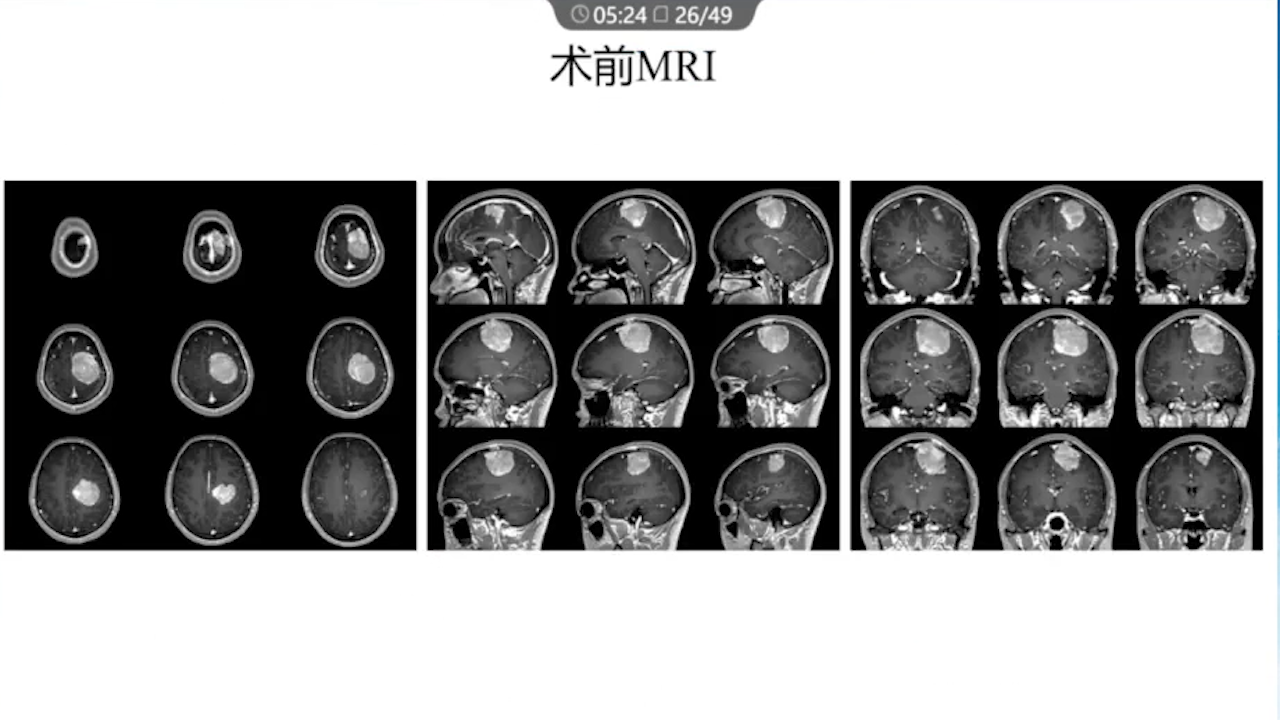

1、术前需要完善的影像学检查、多模态融合及神经导航以进行精确的肿瘤及静脉血管定位。

2、术中硬膜剪开及肿瘤切除时逐步接近功能区,在剪开硬膜前,可行B超定位桥静脉以防误伤,根据桥静脉的位置灵活调整硬膜的剪开方向。

3、在显微镜下用弹簧剪松解桥静脉的蛛网膜束带,使其尽量长的游离。